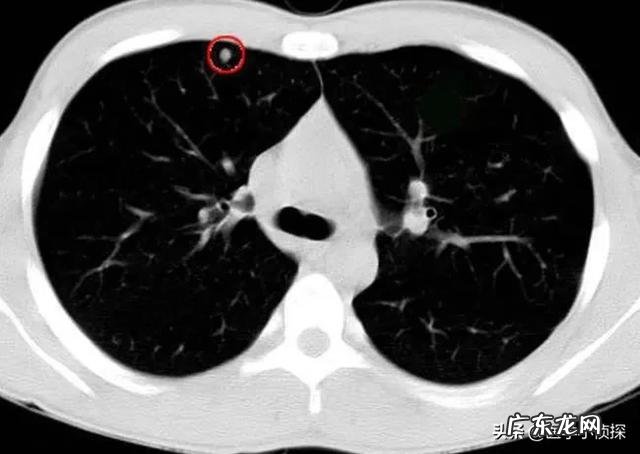

而所谓的恶性特征 , 我们目前比较常遇到就是下面这7种 , 而只要你的肺结节符合4个以上 , 那么我们医生就会告诉你 , 你的这个结节是可疑恶性 , 像这样的结节不再推荐保留 , 通过随访方式来观察 , 最好及时进行手术切除!

diyi种 , 肺结节中出现下面这种分叶征

第二种 , 肺结节周边呈现毛刺征

第三种 , 肺结节有胸膜牵拉征(也叫做凹陷征)

第四种 , 肺结节内部可见如下图类似空泡征

第五种 , 肺结节呈现一种支气管管征

第六种 , 肺结节出现典型的棘状突起

第七种 , 肺结节周围结构集中征 , 尤其是出现了明显的血管向结节聚拢的时候 , 我们要高度警惕恶性的可能 。